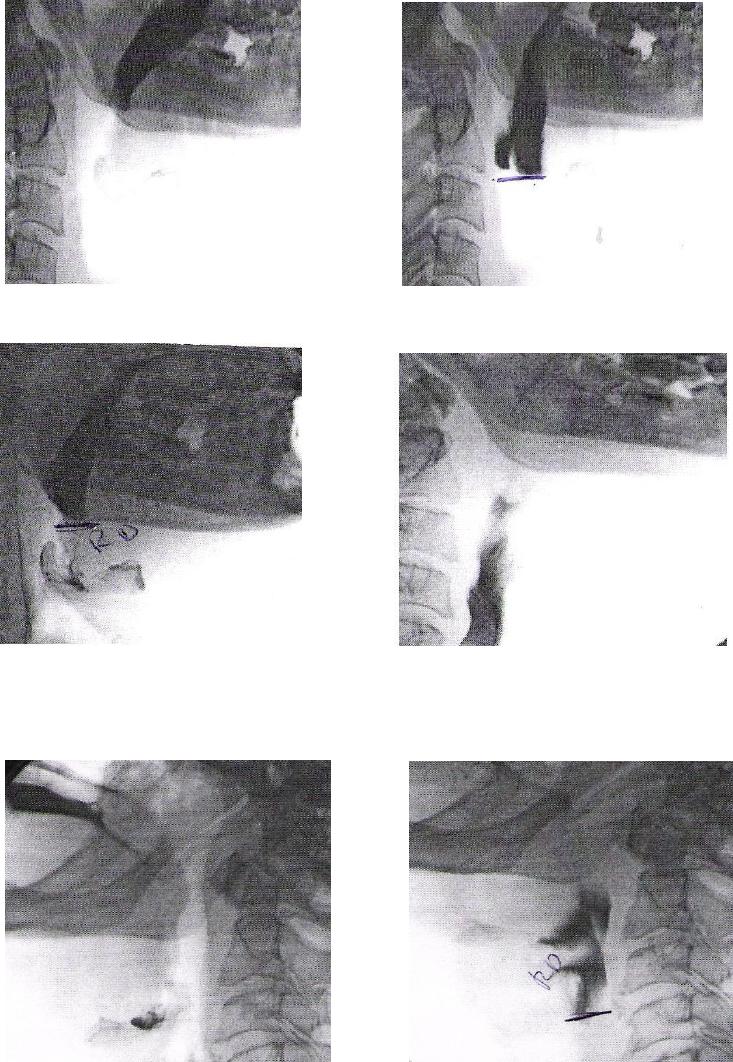

ANEXO E Imagens videofluoroscópicas da deglutição, registrando

escape prematuro e reação de deglutição atrasada, p e s

crioestimulação, com líquido e pastoso.........................................................